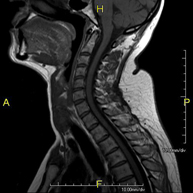

- RM de columna cervical

Prova diagnòstica no invasiva que consisteix en l'obtenció d'imatges d'alta definició anatòmica de la columna cervical mitjançant l'ús d'un camp electromagnètic i ones de ràdio (com un emissor i un receptor). No utilitza radiació ionitzant. Indicacions: traumatisme, degeneració de la columna, hèrnies. - RM de columna dorsal

- RM Columna Cervical

Prueba diagnóstica no invasiva que consiste en la obtención de imágenes de alta definición anatómica de la columna cervical mediante el empleo de un campo electromagnético y ondas de radio (con un emisor y un receptor). No utiliza radiación ionizante. Indicaciones: traumatismo, degeneración de la columna, hernias. - RM Columna Dorsal